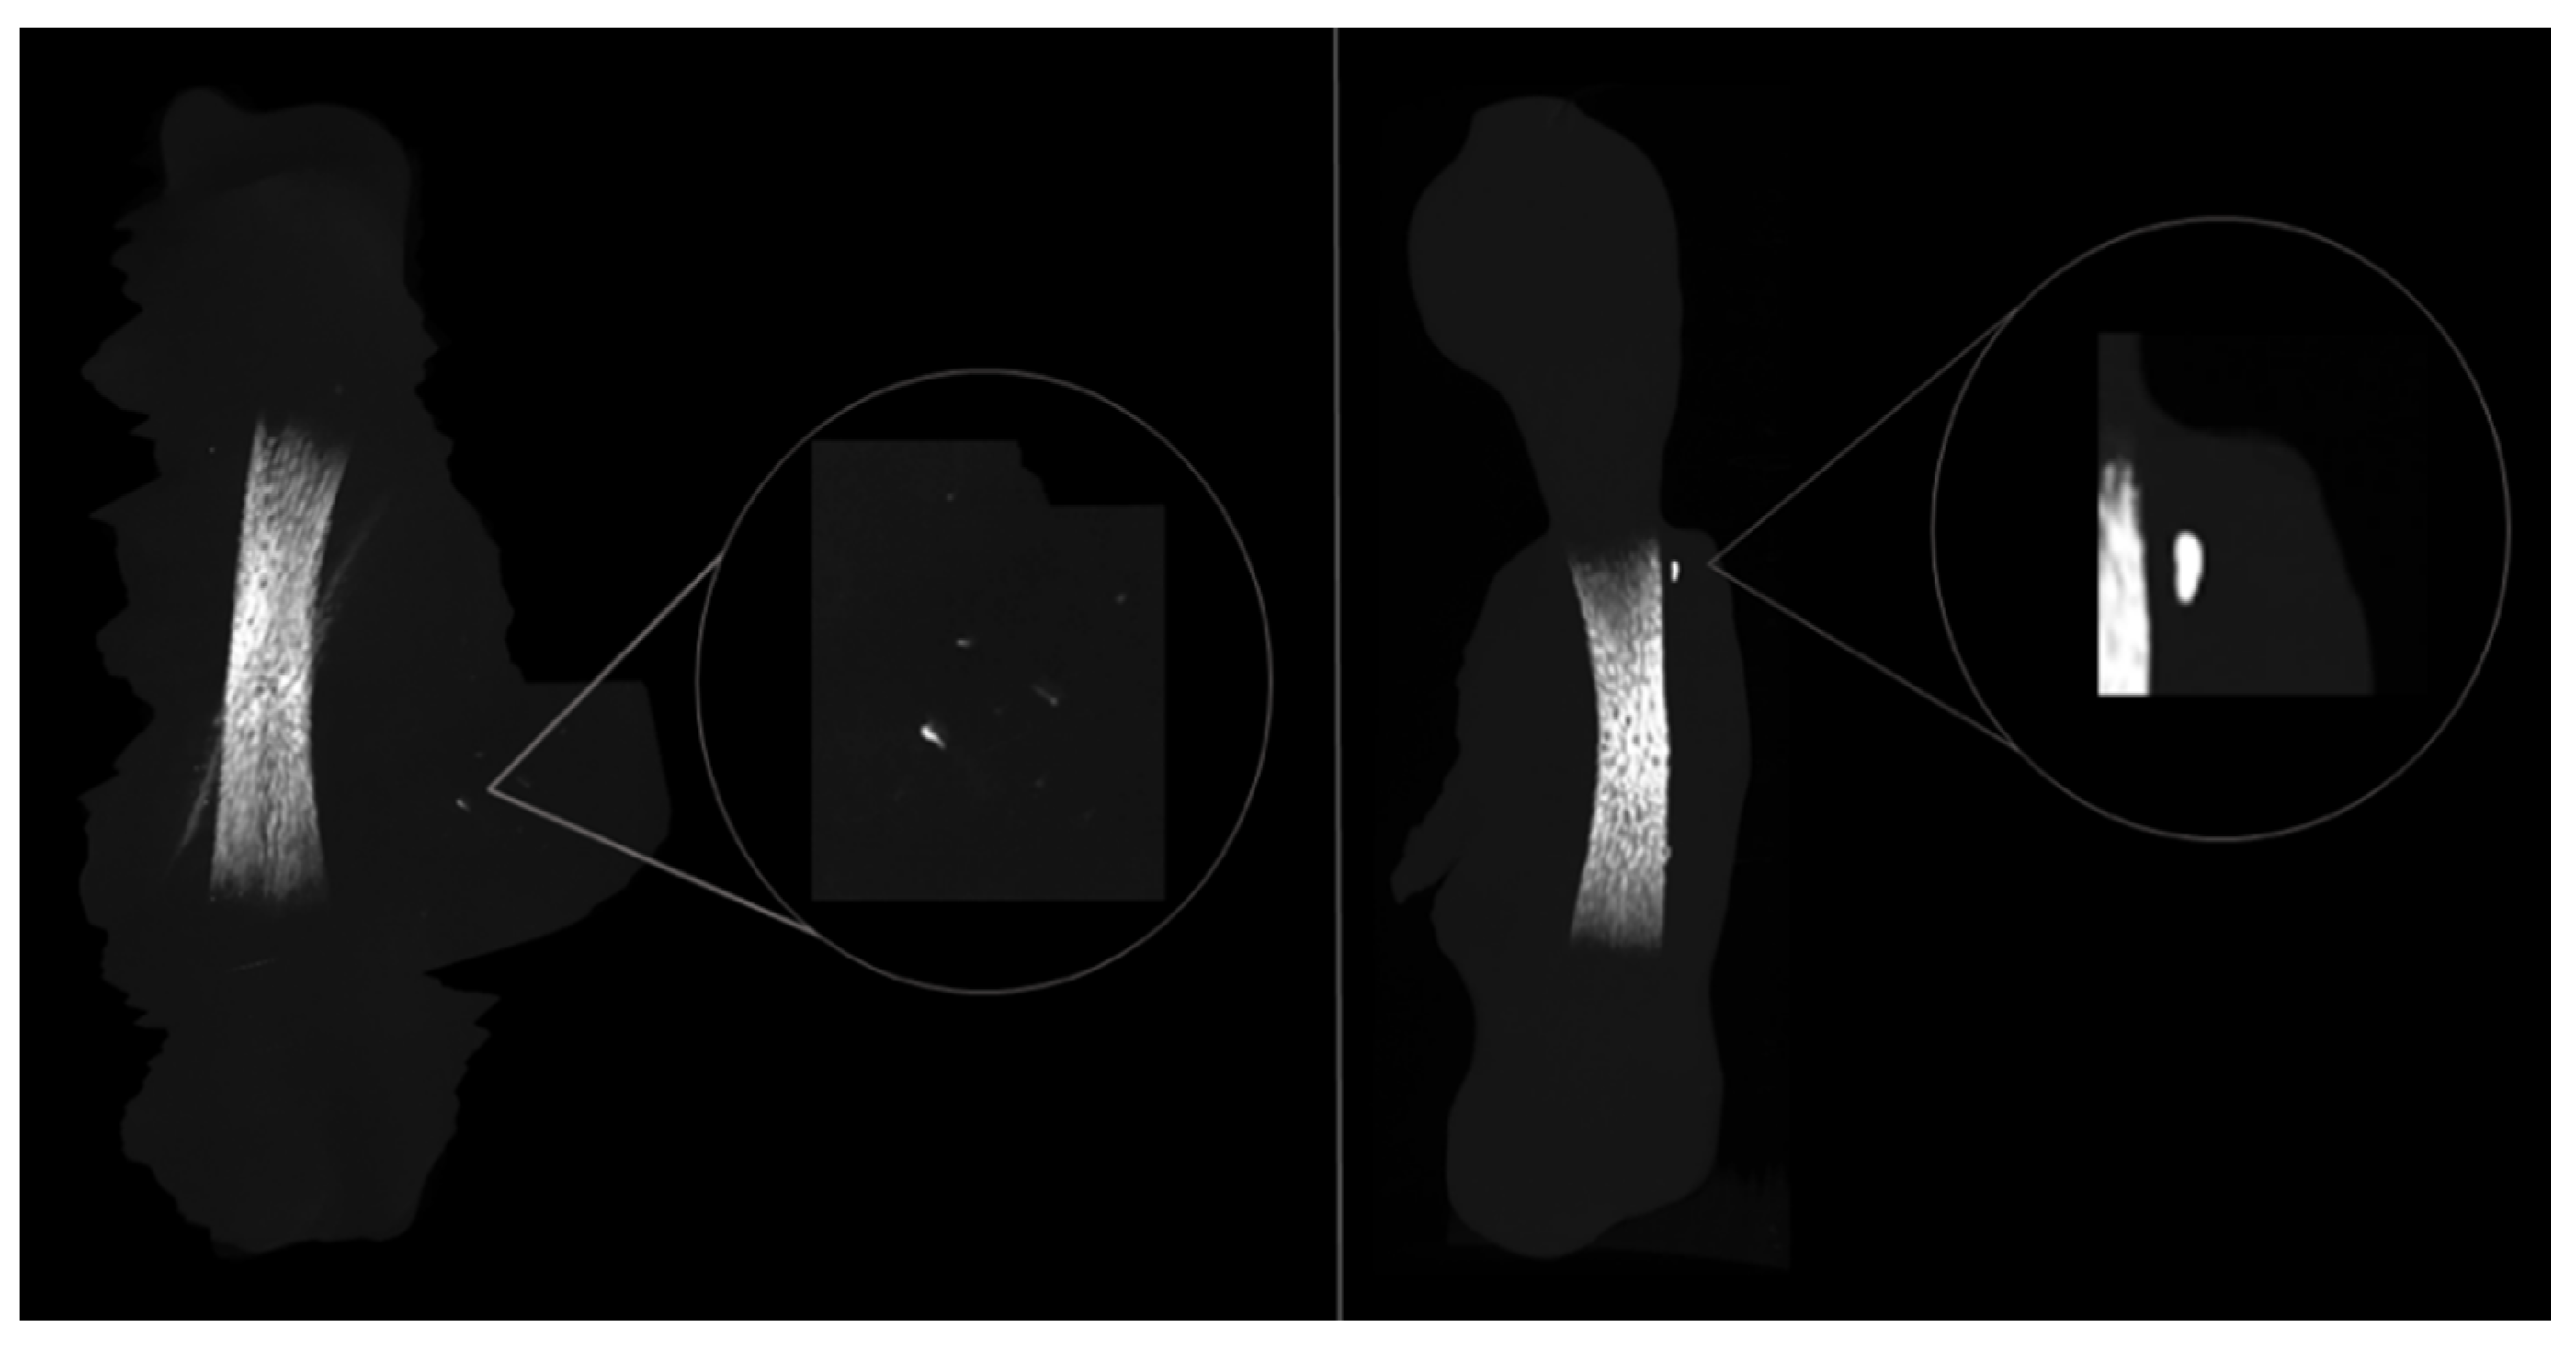

Moreover, during the ROI demarcation for the microcomputed tomographic analysis, mineralized nodules were found within L-PRF membranes in the direct contact group, illustrated by Figure 4. Those nodules were located close to the diaphysis region and were completely decoupled from the femora, suggesting an ectopic mineralization within the structure of L-PRF membrane.

Furthermore, the osteogenic response of the direct contact group occurred mostly in the diaphysis region (Figure 3), and a thicker collagen outer-layer was highlighted by the histochemical staining (Figure 5C) in comparison with the control and the indirect contact groups, representing the mineralized and non-mineralized osteoid matrix [27]. These results are in line with the study by Shawky et al. that studied the effect of PRF in the quality and quantity of unilateral maxillary alveolar clefts, reporting a higher mean amount of newly formed bone volume in the PRF group [37]. In addition, mineralized nodules within the L-PRF membrane were found in the µCT analysis (Figure 4). Aligned with these findings, some collagenous compositions (red stained) were also noted within the L-PRF membrane in the histochemical staining images (Figure 5C), suggesting progressive cellular outgrowth and osteogenic differentiation with the deposition of a collagenous-rich matrix. This was an unexpected result because Knapen et al. reported that connective cells could be seen in the osteotomy region after the application of L-PRF without extending into the L-PRF membrane [38]. The osteogenic induction found by the results of this study may be related to the presence of several growth factors in the L-PRF, namely, the fibroblast growth factor, which induces pre-osteoblasts differentiation and proliferation; VEGF, which enhances angiogenesis and promotes a mitogenic activity and synergy between PDGF with TGF-β, which contributes to the proliferation of cells (marrow stem cells, fibroblasts, pre-osteoblasts) [40]. It is also of note that, in the present experimental model, the L-PRF membrane was placed in direct contact with periosteum, an environment rich in osteoblastic-precursor populations with a high regenerative potential, given the increased clonogenicity, proliferation and osteogenic differentiation capability as compared with bone marrow stromal cells/skeletal stem cells, which may further sustain the enhanced osteogenic outcome [41].

Figure 4. Representative three-dimensional microcomputed images of bone nodules found across the L-PRF membrane in the direct-contact experimental group, emphasising the osteogenic potential of the L-PRF membrane.